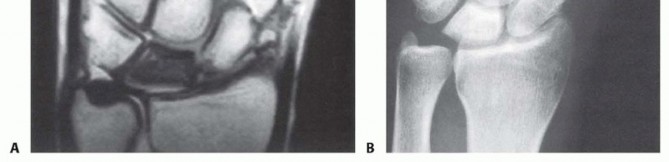

The natural history of Kienböck disease is one of progressive mechanical failure, reliably categorized by the Lichtman classification system. This staging is paramount, as it directly dictates our surgical algorithm. Stage I represents the earliest phase, where standard radiographs appear entirely normal, but magnetic resonance imaging (MRI) reveals the hallmark signs of ischemia: decreased signal intensity on T1-weighted images and variable signal on T2-weighted images, depending on the degree of reactive edema and attempted revascularization.

As the disease advances to Stage II, the lunate begins to exhibit increased radiodensity and sclerosis on plain radiographs. Despite these density changes, the overall anatomical shape and height of the lunate are maintained. This sclerosis represents a combination of compacted necrotic trabeculae and the apposition of new woven bone on dead trabecular cores—a frustrated attempt at creeping substitution. Stage IIIA, our patient's current stage, is characterized by structural failure. The lunate undergoes macroscopic collapse, losing its height and altering its geometry, yet the overall carpal height remains preserved, and there is no fixed scaphoid rotation or proximal migration of the capitate.

If left untreated, the condition relentlessly progresses to Stage IIIB, defined by lunate collapse accompanied by significant carpal instability. This includes a decrease in the carpal height ratio, proximal migration of the capitate into the space vacated by the collapsing lunate, and a fixed palmar flexion of the scaphoid, often visible as the "cortical ring sign" on AP radiographs. Ultimately, the altered kinematics lead to Stage IV, characterized by widespread radiocarpal and midcarpal secondary osteoarthritis. Our goal with the radial shortening osteotomy today is to intercept this natural history at Stage IIIA, preventing the catastrophic transition to Stage IIIB and Stage IV.

Clinical & Radiographic Imaging Archive